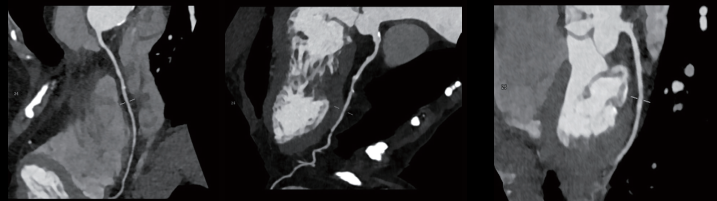

双源CT头颈心联合扫描:头颈部血管显示清晰,未见明显异常。